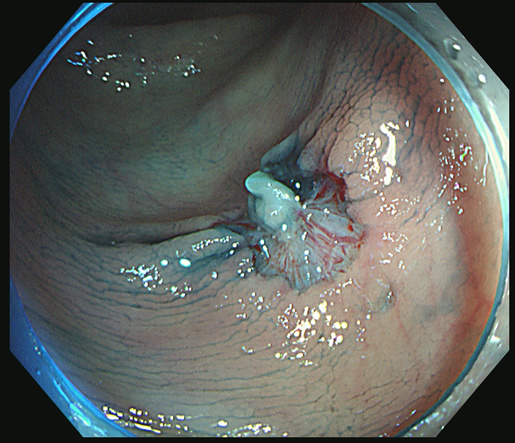

カンシで右上方向を追加切除します

細胞を1個も残さないことが肝要です。

1個でも残れば再発し、やがて癌化します!